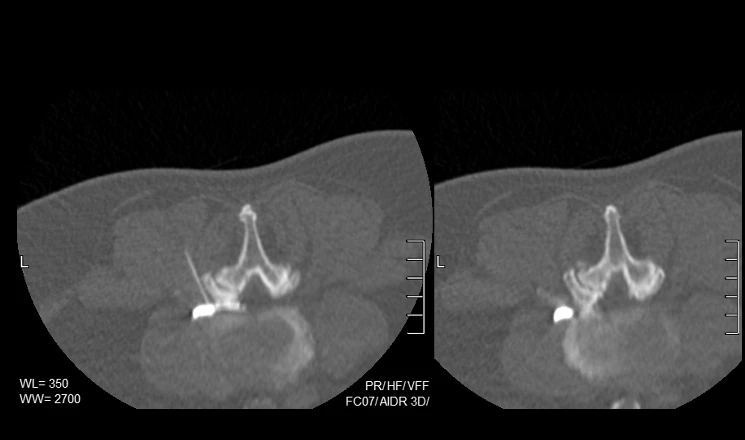

Using real-time imaging such as ultrasound, fluoroscopy, or CT, targeted injections and interventions are delivered with high accuracy—helping reduce pain, improve mobility, and restore quality of life.

At Vikash IR Clinic, Bangalore, interventional pain management is offered after a careful clinical and imaging-based evaluation to identify the exact pain generator. The site of pain is targeted precisely using ultrasound or CT and the affected sites are treated with injections or ablations.